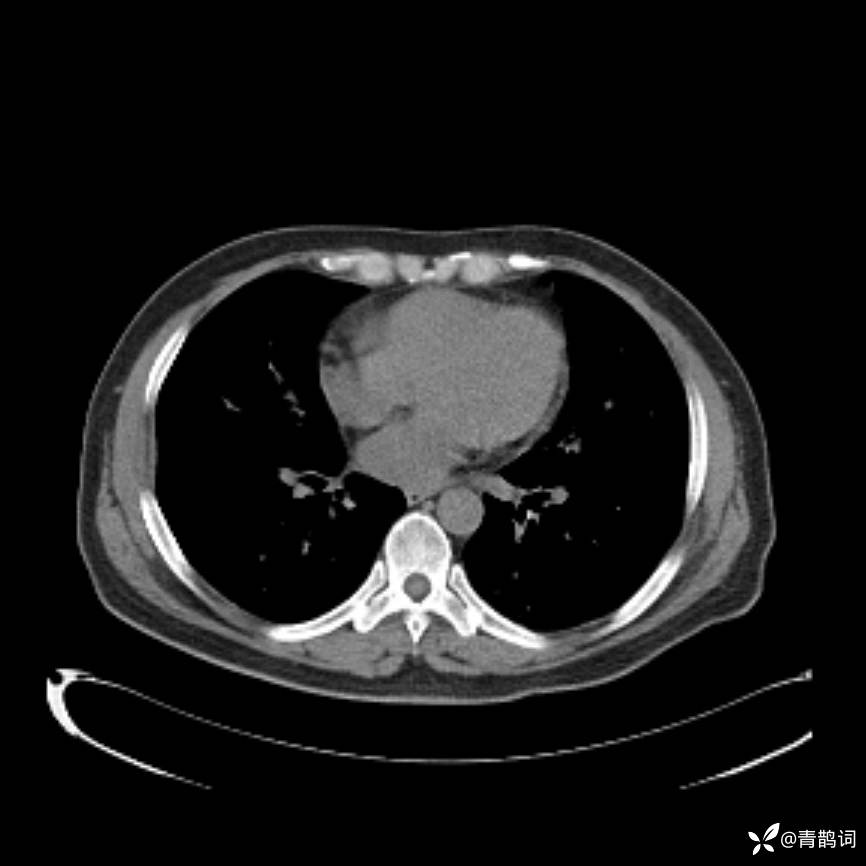

患者年龄:30岁。

患者性别:男。

简要病史:左颜面部肿胀2年,反复咳嗽咳痰,逐渐加重。

辅助检查

结合病史及影像学表现,期待评论区各位老师各抒己见~